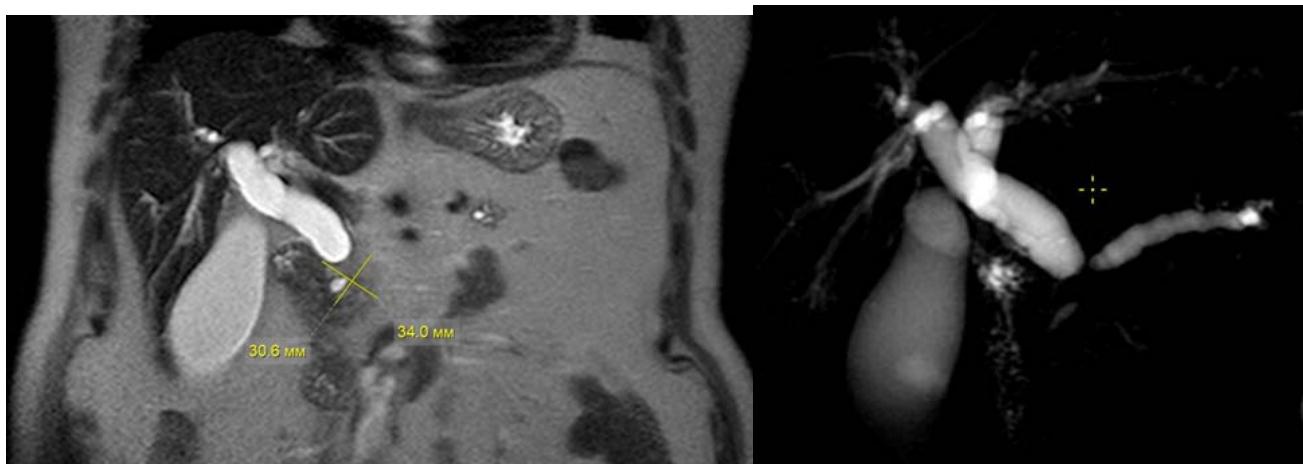

Fig. 7: MRI-characteristics of a tumour of the head of the pancreas Fig. 6: Device for trephine biopsy of tumours of the head of the pancreas and the distal common bile ductbyE.B.Revazov-Ts.S.Khutiev

To determine the technical aspects of performing trephine biopsy, we performed a continuous retrospective analysis from a database of 100 contrast-enhanced MRIs of the abdominal cavity in patients with a tumour of the head of the pancreas and biliary hypertension (Fig. 7). Studied the size and preferential localization of the tumour in relation to the hepaticocholedochus (HC), its relationship to the main pancreatic duct (MPD) and duodenum (DU). The age of the patients was 35-90 years, with average of $65 \pm 1,13$. Men - 54 (54%), women - 46 (46%).

<table><tr><td>Sign</td><td>Minimum</td><td>Maximum</td><td>Average</td></tr><tr><td>Tumour size (mm)</td><td>11</td><td>89</td><td>35.4±1,53</td></tr><tr><td>Diameter of hepaticocholedochus (HC)(mm)</td><td>7.5</td><td>35</td><td>15,6±0,51</td></tr><tr><td>The length of the tumour narrowing of the HC(mm)</td><td>4</td><td>50</td><td>27±1,1</td></tr><tr><td>Hepaticocholedochus angle (degrees)</td><td>80</td><td>162</td><td>115,3±1,69</td></tr><tr><td>Diameter of the main pancreatic duct (MPD)(mm)</td><td>2</td><td>18</td><td>7,3±0,37</td></tr><tr><td>Distance from the level of the HC block to the level of the MPD block (mm)</td><td>1</td><td>63</td><td>11,9±1,02</td></tr><tr><td>Length from the proximal border of the HC block to the duodenum (mm)</td><td>14</td><td>52</td><td>30,8±0,91</td></tr></table>

Tumour size varied from 11 to $89\mathrm{mm}$, averaging $35,4 \pm 1,53\mathrm{mm}$. According to the TNM system in stages $T_{1} - 4$, $T_{2} - 60$, $T_{3} - 32$, $T_{4} - 4$ patients. Signs of germination in the duodenum and MDP were noted in 18 (18%) patients; limited to invasion of parapancreatic tissue in 7 (7%) patients. Enlarged regional lymph nodes in 14 (14%) patients. Distant metastases were detected in 28 (28%) patients. Of them: $T_{1} - 2$, $T_{2} - 10$, $T_{3} - 15$, $T_{4} - 1$.

The diameter of the hepaticocholedochus (HC) ranged from 7,5 to $35\mathrm{mm}$, on average $-15,6\pm 0,51\mathrm{mm}$; the length of the tumour narrowing of the HC is from 4 to $50\mathrm{mm}$, the average is $27\pm 1,1\mathrm{mm}$. In 19 (19%) cases, an intact distal part of the common bile duct was identified extending from 5 to $36\mathrm{mm}$. The length from the proximal border of the HC block to the duodenum along the HC axis is $14 - 52\mathrm{mm}$, on average $-30,8\pm 0,91\mathrm{mm}$.

The HC angle in the distal third was $80 - 160^{\circ}$ with an average of $115,3\pm 1,69^{\circ}$. The magnitude of the angle depended on the predominant localization of the tumour, the degree of biliary hypertension and the associated elongation of the HC and its tortuosity. Currently, there is no clear understanding of the dependence of technical actions on a simple statement of the value of the angle HC. The opinion of an individual approach to this parameter and its further study remains.

The diameter of the main pancreatic duct (MPD) is from 2 to $18\mathrm{mm}$, on average $-7,3 \pm 0,37\mathrm{mm}$. The absence of pancreatic hypertension was noted in 14 $(14\%)$ patients, including 4 $(4\%)$ with a tumour size more than $40\mathrm{mm}$. 27 $(27\%)$ had MPD from 3,5 to $6\mathrm{mm}$ and 57 $(57\%)$ had $6\mathrm{mm}$ or more. In 2 $(2\%)$ MPD was not possible to visualize due to the extensive of the tumour process in the pancreas.

The distance from the HC block level to the MPD block level ranged from 1 to $63 \mathrm{~mm}$, with an average of $11,9 \pm 1,02 \mathrm{~mm}$. In 26 (26%) patients this distance is less than $7 \mathrm{~mm}$ and in 13 (13%) of them the

MPD diameter is 6mm or more. Erosion of the internal contour HC in the area of the block was detected in 35 (35%), of which in 17 (17%) – like a "writing pen", in 9 (9%) – on the lateral side, in 9 (9%) – on the medial side; in 65 (65%) a "transverse block" is determined. There is no unambiguous connection between the predominant localization of the tumour and the size of HC contour usuration. Preferential location of the tumourabout HC: antemedial – 49 (49%), antegrade – 18 (18%), circular – 20 (20%), medial – 6 (6%), antelateral – 5 (5%), latero-antemedial – 2 (2%). In 67 (67%), the tumour thickness anterior to the HC lumen was more than 10 mm (Fig.8, 9, 10).